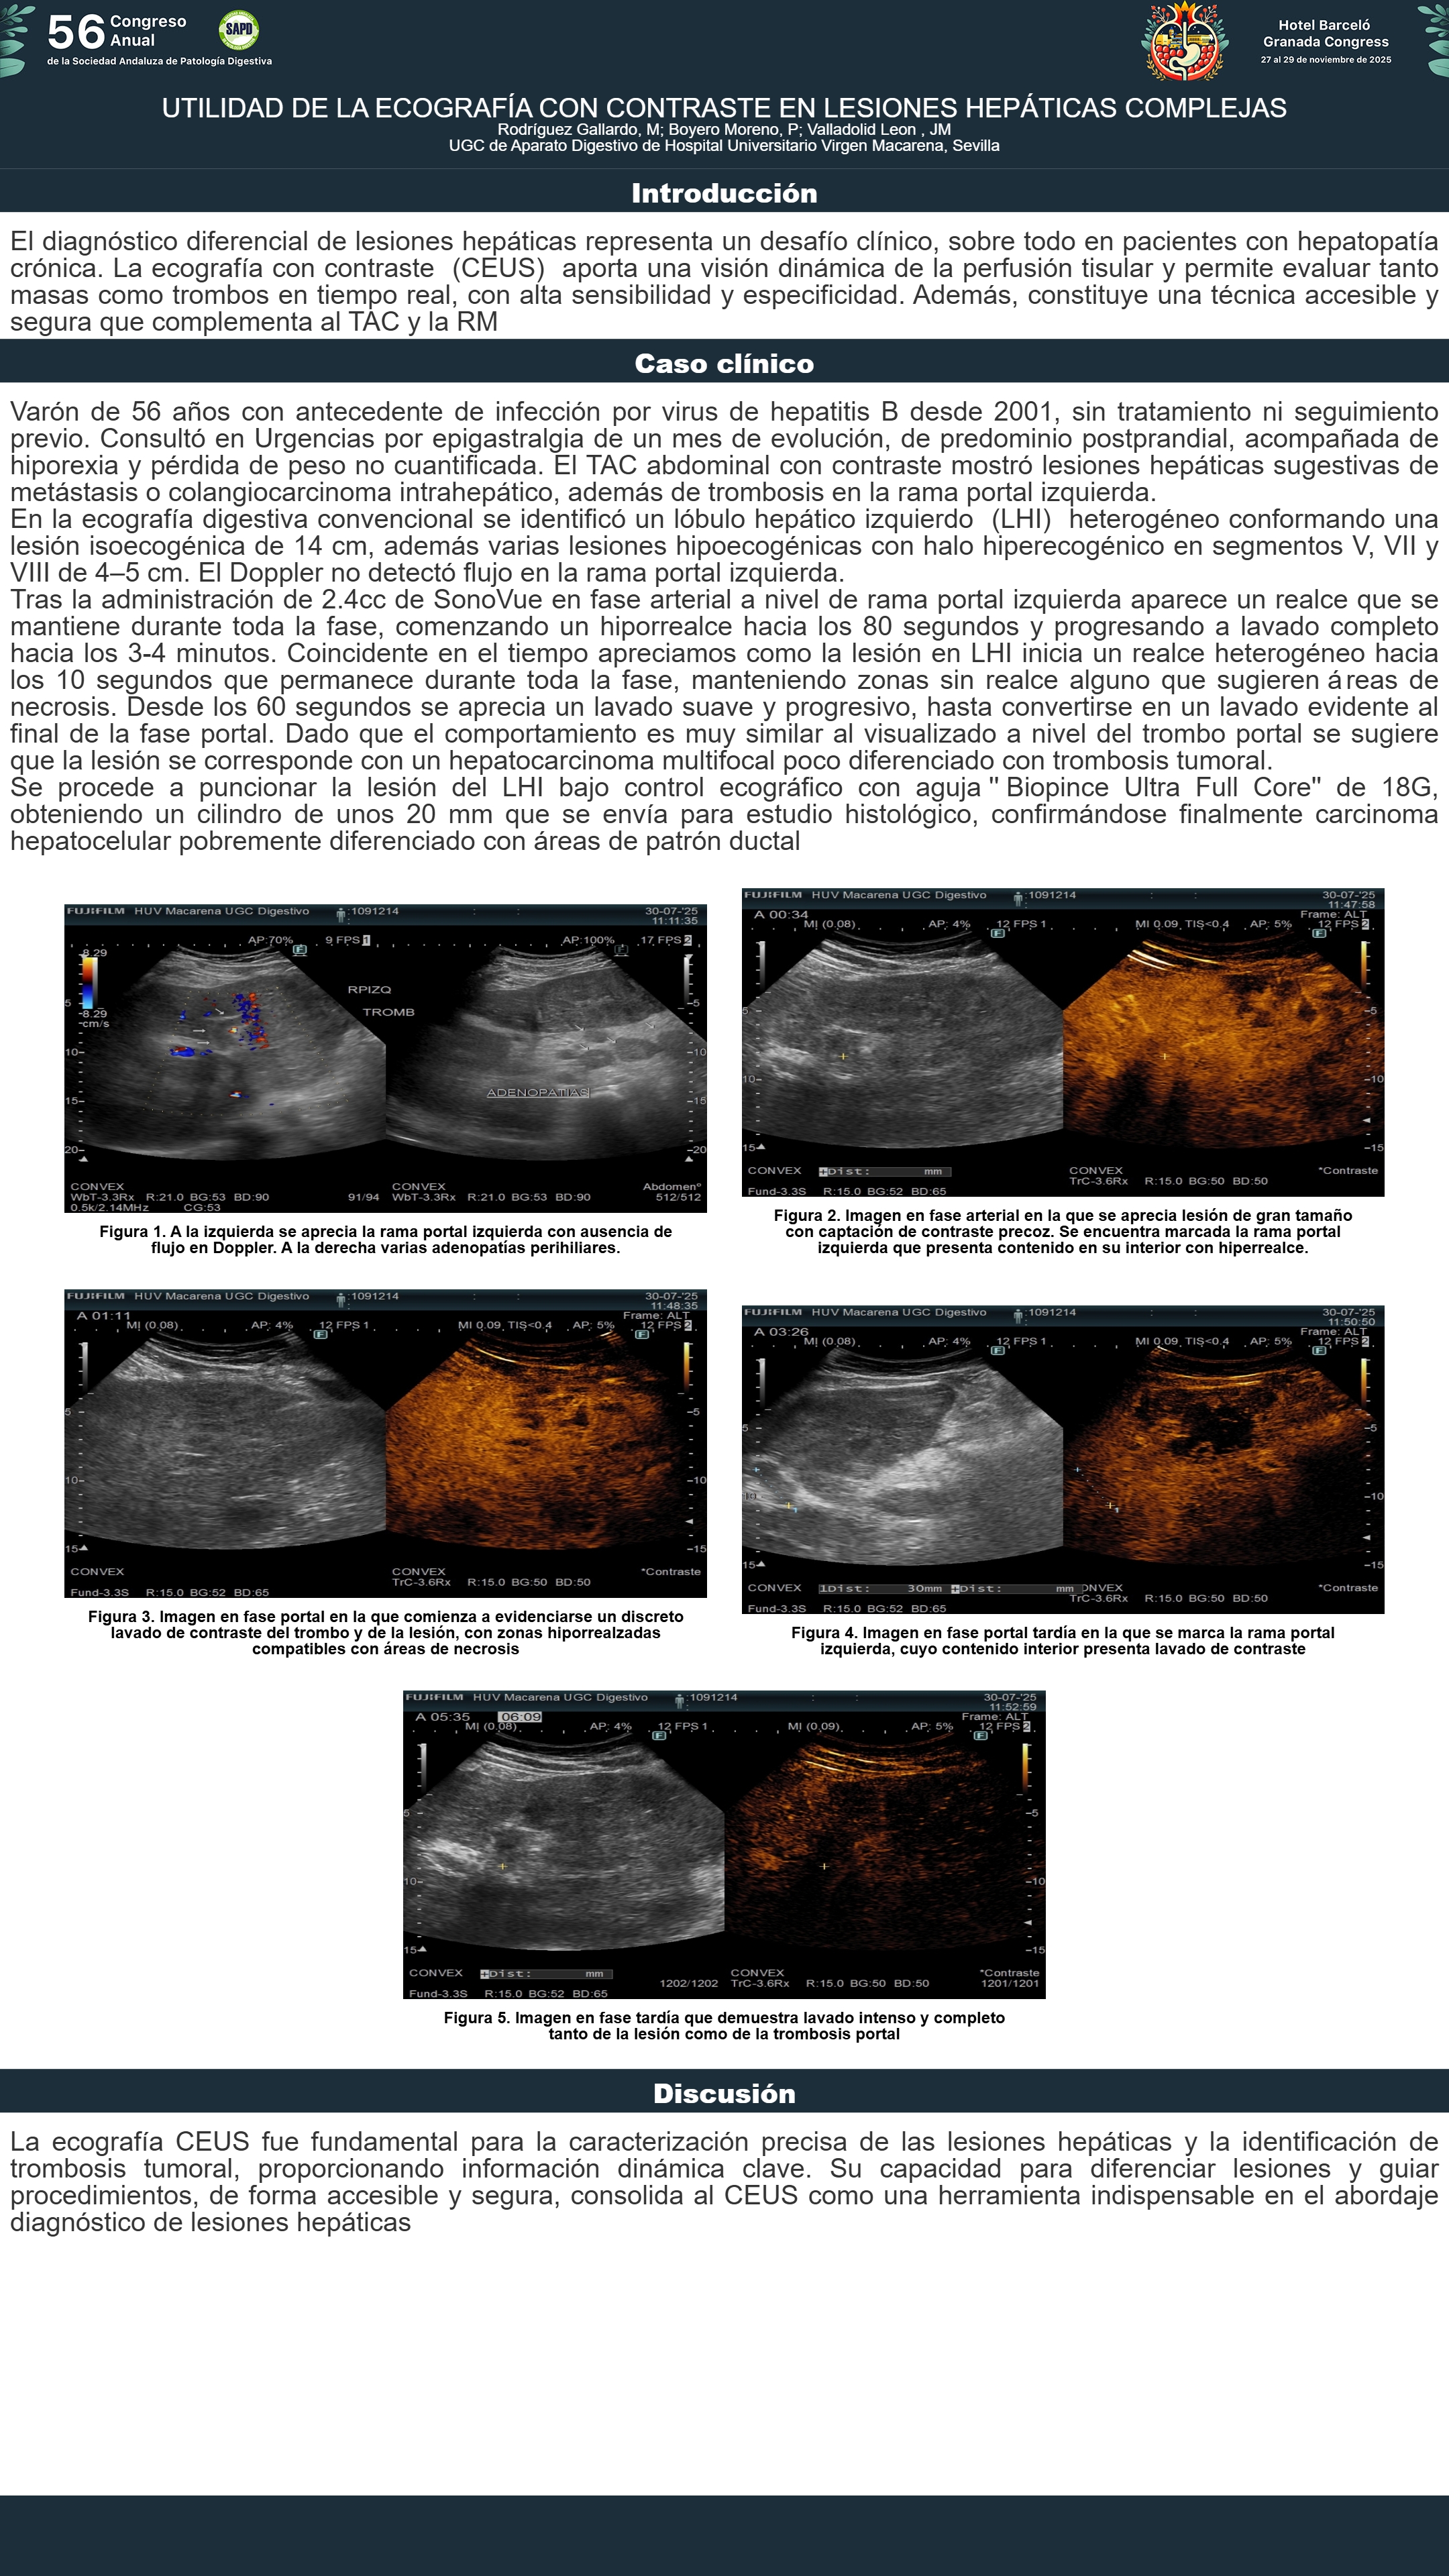

[CP-073] UTILIDAD DE LA ECOGRAFÍA CON CONTRASTE EN LESIONES HEPÁTICAS COMPLEJAS